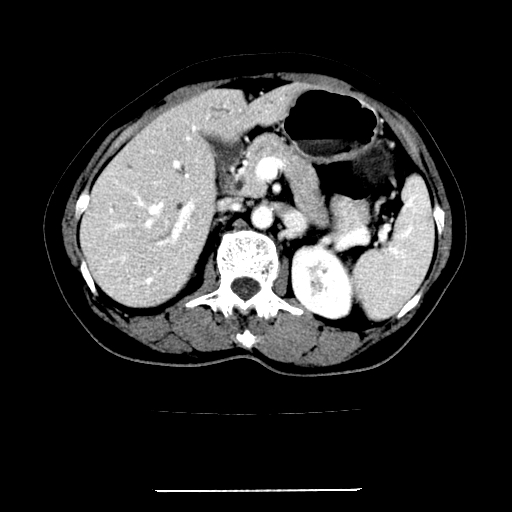

女,67岁,上腹部疼痛一周伴皮肤黄染,无发热。

左叶肝内胆管结石,并远端肝内胆管扩张。

考虑:肝内胆管结石继发肝内胆管扩张,右肾旋转不良。

肝内外胆管结石并肝内胆管扩张。

1、肝门高密度影下层面和胰头层面可见轻度胆管扩张,而静脉和延迟期均未见扫描完胰头,不能完全排除胰头占位。2、肝门部高密度影,考虑钙化或结石。

考虑肝门胆管癌伴门脉左支受侵包埋,建议mrcp进一步检查。